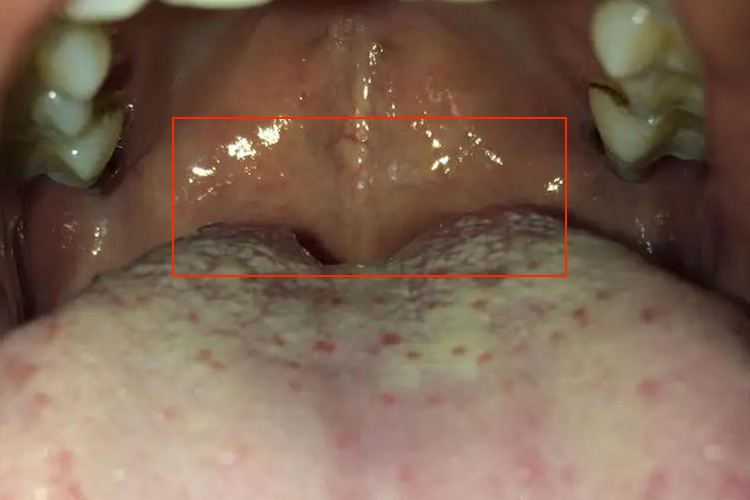

舌头根部有小疙瘩可能是正常的轮廓乳头、叶状乳头,也可能是舌乳头炎、口腔单纯疱疹、慢性咽炎、舌根肿瘤等疾病。发现后勿自行处理,应及时就医诊断和治疗。

- 炎症蔓延至舌根部位,可能导致淋巴滤泡增生,表现为舌根的小疙瘩,常有咽部异物感、咽干、咽痒等,针对咽炎进行治疗,如使用含片、雾化吸入等。